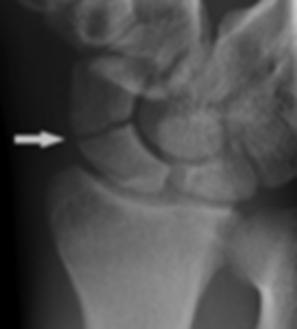

Fractura de escafoides

Es el hueso del carpo más fracturado, el mecanismo es por caída en dorsiflexión. La mayoría ocurre a nivel del cuello.

Imágenes: la radiografía en los primeros días es poco sensible por lo que se prefiere la TAC, en caso se requiera diagnóstico precoz.

Las complicaciones más frecuentes son:

Necrosis avascular proximal Pseudoartrosis